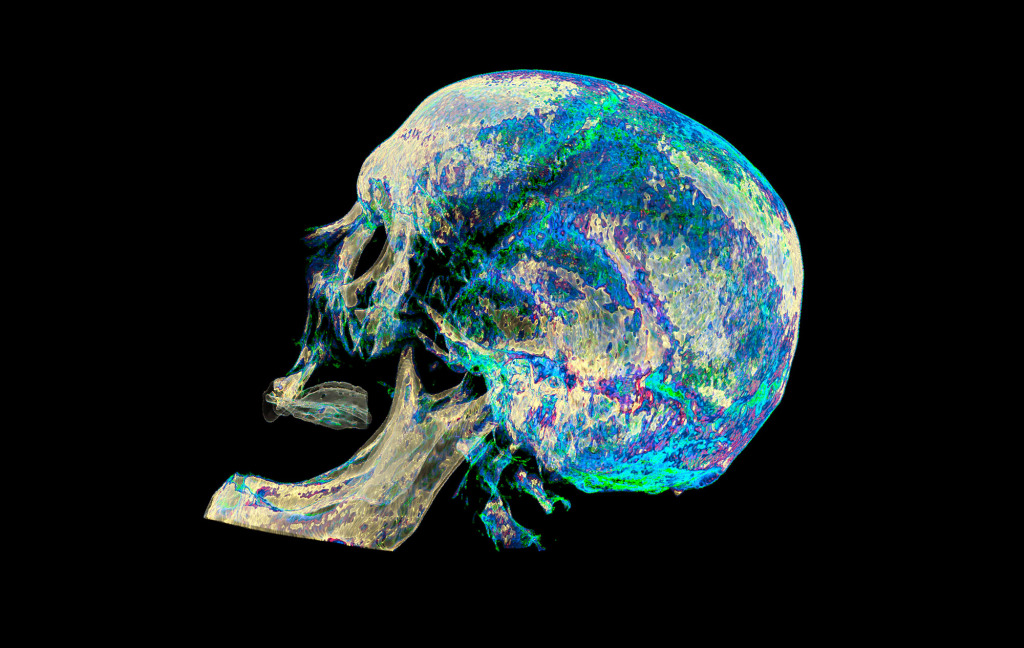

Vsevolod works as a radiologist at Oleksandrivska Clinical Hospital, the oldest hospital in Ukraine. Coming from a medical family it seemed inevitable that he would join the profession. Radiology opened a whole new world enabling him to visualise the delicate structures of the human body.

He began to experiment with different perspectives and colours, adding a creative spark to his professional work. At the moment, his country is facing challenging war time conditions, but Vsevolod still manages to create stunning content.

At a lecture on radiology I saw a simple 3D visualisation of a CT examination for the first time. It made an impression on me and the same day at home I started looking for information and software for independent processing of DICOM images. After a few hours, I managed to get a three-dimensional image.

A multi-coloured, bright image is a way to shift the gaze and perceive things differently.

Also, I like to experiment with different photo filters and settings.

The program for processing radiological images (DICOM archives) allows you to create and look at a three-dimensional image from different angles.

If you change the location of the virtual lens, thereby changing the perspective, you can get such images.

How do you decide which colours to use on the images?

The colours choose themselves.

I simply create a table where the radiological density of the material can correspond to any colour.

After combining different shades, I only have to choose what I like the most.